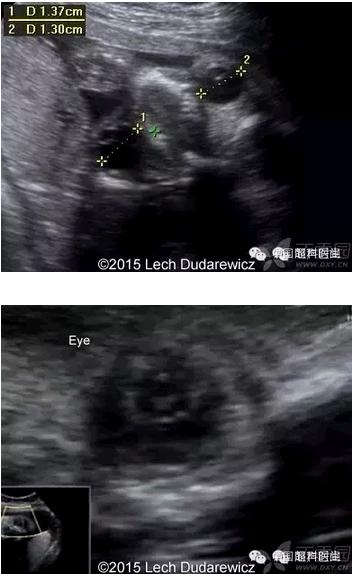

图 3 为以往某孕 15 周的先天性白内障;图 4 为本例孕妇 34 周先天性白内障及永存玻璃体动脉

图 5 为胎儿眼部超声所见:眼球过小,白内障,晶状体回声增强,其后方可见残存的玻璃体动脉;lens:白内障;hyaloid artery:玻璃体动脉;图 6 为正常胎儿眼球的对照图像,注意其晶状体回声与图 5 的差别